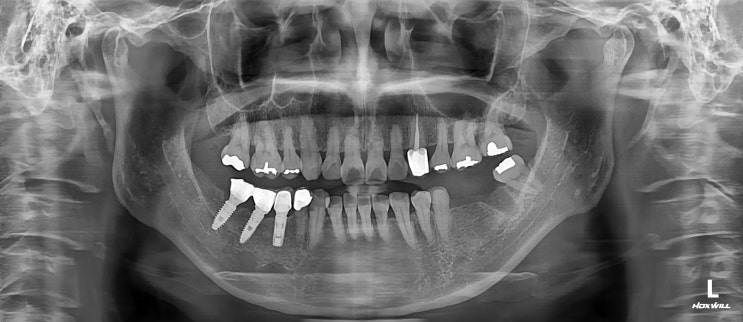

[세곡동 치과] 얇은 뼈 임플란트 식립

안녕하세요 세곡동 치과 수서동 치과 보철과 전문의 수서서울삼성치과 대표원장 이재현입니다 오늘은 얇은 ...